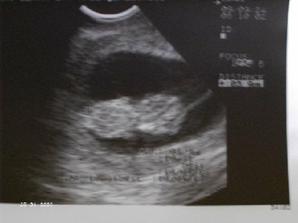

24.9. mě čeká další kontrola, prý už uvidím malého človíčka...tak človíčka jsem viděla,odpovídal 10+3tt, přesně podle poslední MS, mrňous mrskal rukama a nohama a od hlavičky k zadečku měří 4 cm 🙂 , dostala jsem těhotenskou průkazku a TERMÍN PORODU je stanoven na 16.4. 2010.